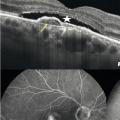

Dans la DMLA exsudative, les néovaisseaux sont visibles comme des lésions fusiformes hyper- réflectives, ainsi que leur activité : décollement séreux rétinien et logettes d’œdème intrarétiniennes (fig. 5 ).

Commercialisé en 2015, cet examen prend une place grandissante. L’appareil utilise une technique dérivée de l’OCT qui mesure la vitesse des hématies et donne des images non invasives du flux vasculaire. Il est particulièrement intéressant dans la forme exsudative, en montrant les néovaisseaux choroïdiens sans nécessiter l’injection de produits de contraste (fig. 5 ). L’association à l’OCT classique permet de visualiser leur activité (DSR, œdème). à l’avenir, il est possible que l’angio-OCT se substitue à l’angiographie à la fluorescéine pour le diagnostic de DMLA exsudative.

Angiographie à la fluorescéine et au vert d’indocyanine

Historiquement, l’angiographie à la fluorescéine est le gold standard du diagnostic et du suivi des DMLA exsudatives. Des photos du fond d’œil sont réalisées après injection d’un colorant fluorescent par voie intraveineuse. Il révèle les vaisseaux rétiniens et les signes indirects de perméabilité des néovaisseaux choroïdiens. On peut lui associer le vert d’indocyanine en cas de doute diagnostique ou de forme particulière de DMLA (fig. 5 ). Toutefois, des réactions d’hypersensibilité ont été rapportées avec la fluorescéine : chocs anaphylactiques qui ont parfois conduit au décès des patients. Ce risque impose un interrogatoire précis et une éventuelle prémédication anti-allergique. L’intérêt de l’examen est donc de plus en plus discuté. L’angio-OCT, indiqué en 2e intention en cas de doute diagnostique, pourrait le détrôner.